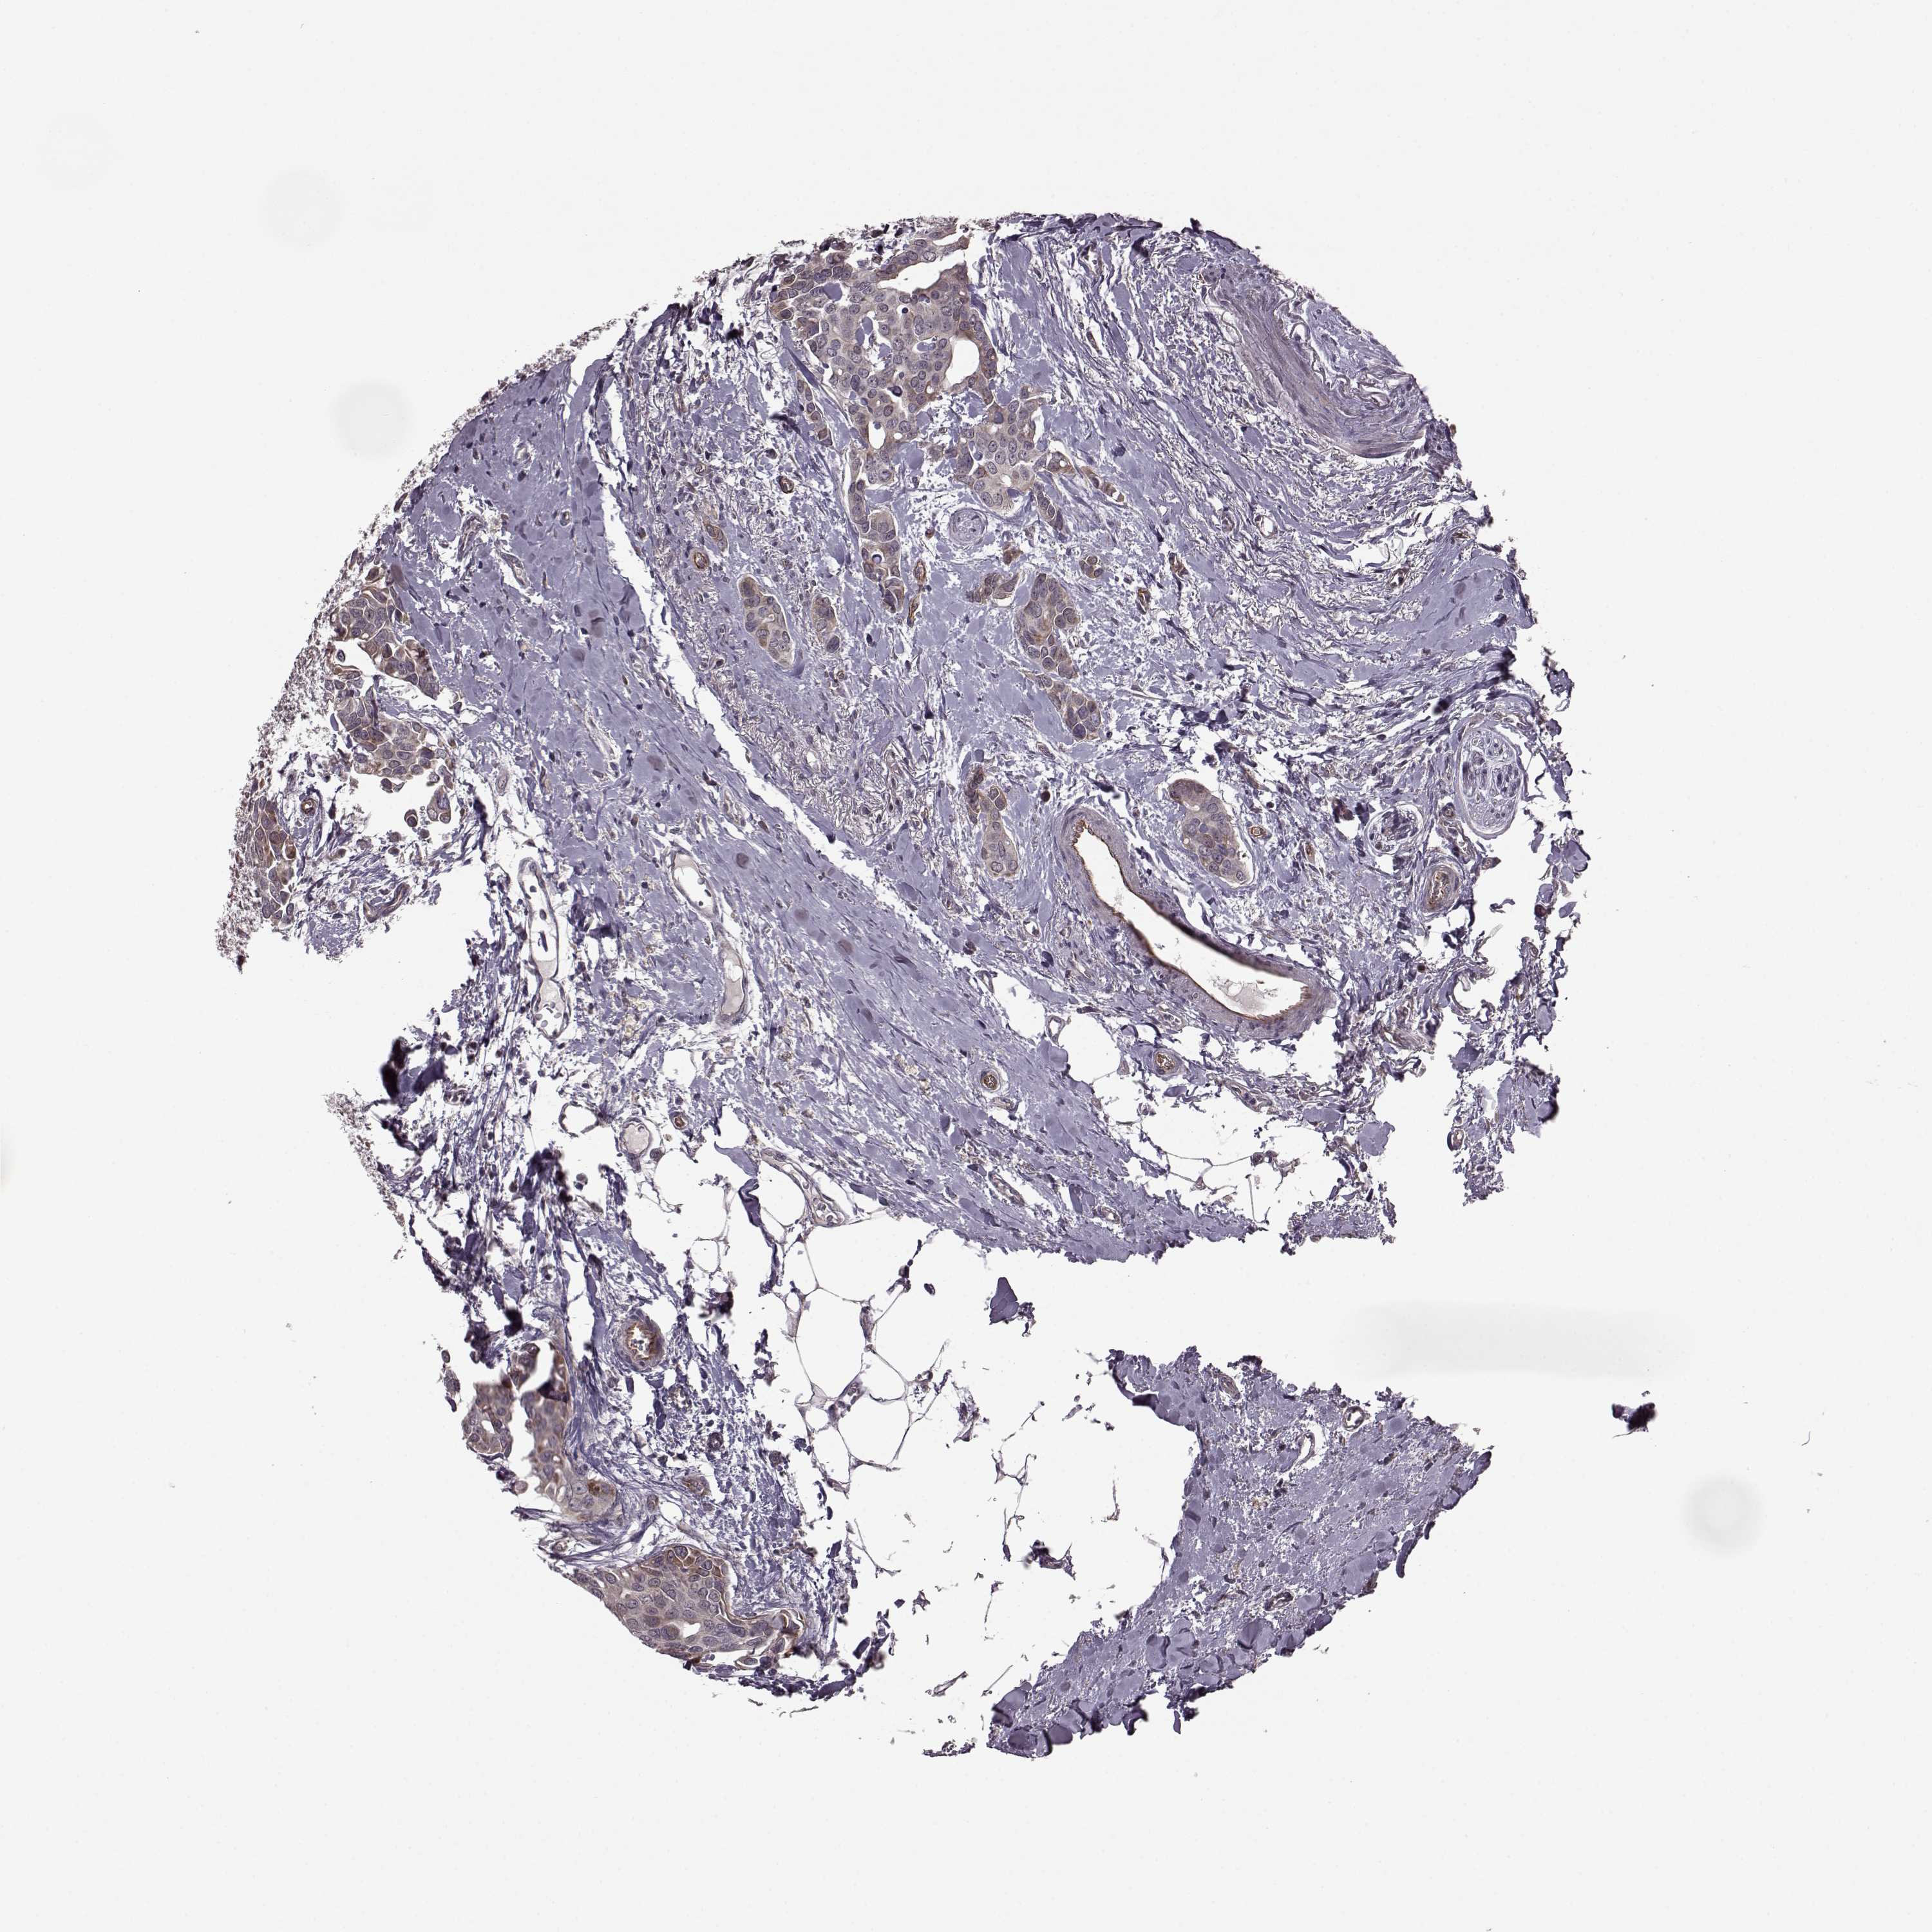

CANCER BREAST CANCER Show tissue menu

BRCA TCGA BRCA VALIDATION PROTEIN EXPRESSION

ANTIBODIES

AND

VALIDATION